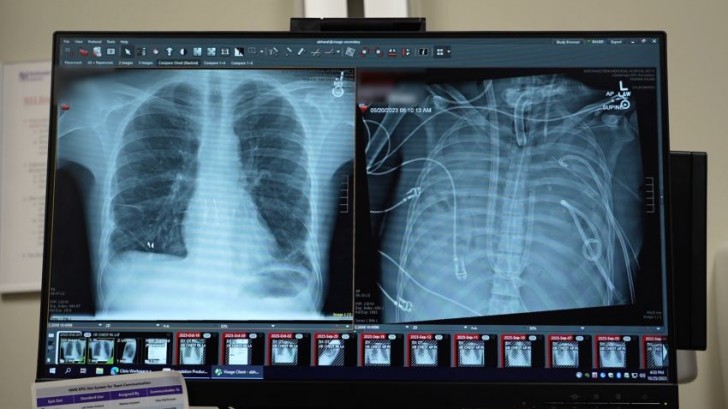

Rade Tomic, directeur du programme de transplantation de Northwestern, a expliqué : « Ses poumons étaient tellement gravement infectés qu'ils ont commencé à se liquéfier. Sa radiographie montrait qu'il ne restait rien : les poumons étaient complètement remplis de pus. Lorsque nous avons reçu un appel de l'équipe médicale de Davey, de St. Louis, nous pensions que nous pourrions l'aider, mais il était également très clair qu'il ne survivrait pas à la greffe dans ses conditions actuelles. »